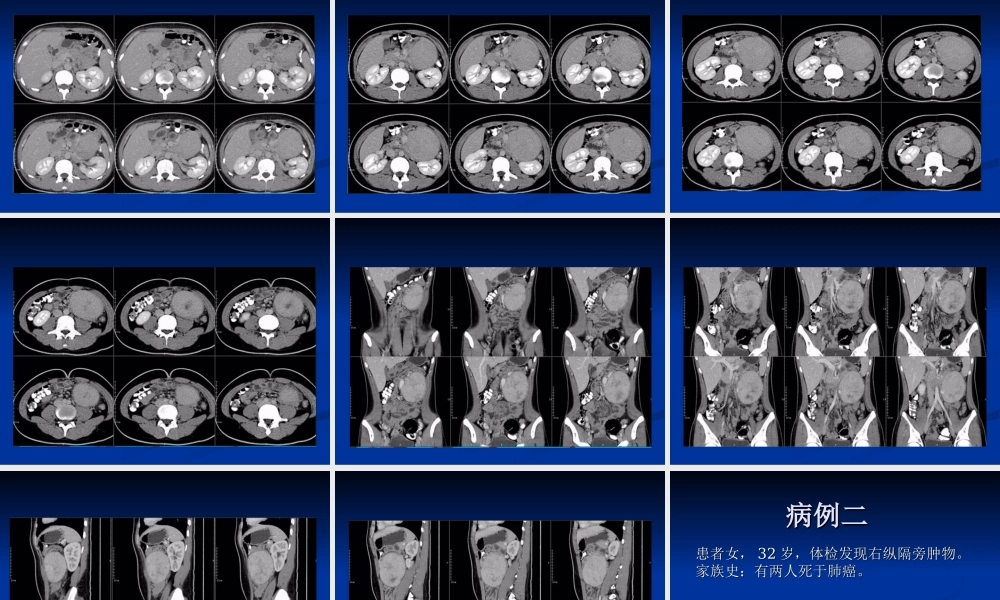

病例一病例一男,男,1616岁,无明显诱因出现左上腹疼痛,岁,无明显诱因出现左上腹疼痛,呈阵发性绞痛,每次发作持续约呈阵发性绞痛,每次发作持续约1-21-2分钟后分钟后自行缓解,无呕吐、腹泻、黑便,肛门排气、自行缓解,无呕吐、腹泻、黑便,肛门排气、排便正常。排便正常。左上腹触及一约左上腹触及一约10×10cm10×10cm大小包块,质大小包块,质硬,边界清,活动度尚可,压痛阳性,肠鸣硬,边界清,活动度尚可,压痛阳性,肠鸣音正常。音正常。彩超:左上腹低回声肿块,边界清,内部回彩超:左上腹低回声肿块,边界清,内部回声不均,其内及周边可见丰富血流信号。声不均,其内及周边可见丰富血流信号。病例二病例二患者女,患者女,3232岁,体检发现右纵隔旁肿物。岁,体检发现右纵隔旁肿物。家族史:有两人死于肺癌。家族史:有两人死于肺癌。??巨淋巴结增生症巨淋巴结增生症巨淋巴结增生症巨淋巴结增生症(GLNH)(GLNH)是一种少见病,是一种少见病,病因尚不明确,患者多无症状,为异源性病因尚不明确,患者多无症状,为异源性的罕见的淋巴组织增生性疾病,亦称为血的罕见的淋巴组织增生性疾病,亦称为血管滤泡性淋巴组织增生。管滤泡性淋巴组织增生。GLNHGLNH于于19541954年由年由CastlemanCastleman首先发现,故又称其为首先发现,故又称其为CastlemanCastleman病。病。19561956年确定为良性非肿瘤性病变。年确定为良性非肿瘤性病变。发病与病因发病与病因GLNHGLNH自自19541954年发现以来,关于年发现以来,关于GLNHGLNH的病因尚存在两种不同的学说的病因尚存在两种不同的学说::第一种认为本病表现为反应性淋巴组织增第一种认为本病表现为反应性淋巴组织增生,与慢性抗体刺激有关,可能为病毒感生,与慢性抗体刺激有关,可能为病毒感染所致。染所致。第二种理论则认为透明血管型是一种淋巴第二种理论则认为透明血管型是一种淋巴组织的进行性生长紊乱,而浆细胞型的发组织的进行性生长紊乱,而浆细胞型的发生与生与IL-6IL-6调节障碍有关。调节障碍有关。病理病理在病理上可分为透明血管型和浆细胞型两种类型在病理上可分为透明血管型和浆细胞型两种类型透明血管型:特征为淋巴滤泡退化和毛细血管数透明血管型:特征为淋巴滤泡退化和毛细血管数量增加。突出的变化有:肿胀的血管内皮、外皮量增加。突出的变化有:肿胀的血管内皮、外皮细胞以及生发中心内的少量网状细胞可排列成同细胞以及生发中心内的少量网状细胞可...